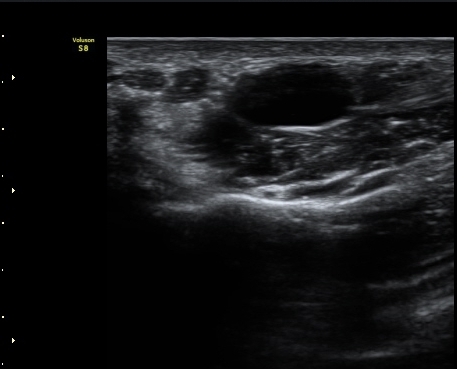

¼ö±Ù°ü¸»´Ü(trapezium ±âÁØ) Á¤Á߽Űæ Ⱦ´Ü¸é°Ë»ç¿¡¼­ Á¤Á߽ŰæÀÇ Àú¿¡ÄÚ ºÎÁ¾ÀÌ °üÂûµÈ´Ù(±×¸² 3)

ÀÌ´Â Åë»óÀûÀÎ ¼ö±Ù°üÁõÈıº¿¡¼­ º¸ÀÌ´Â ¾ç»ó°ú ´Ù¸¥ ¸ð½ÀÀÌ´Ù.

ŽÃËÀÚ¸¦ Á¶±Ý ´õ ¸»´ÜÀ¸·Î À̵¿ÇÏ´Ï Á¤Áß½Å°æ ½ÉºÎ¿¡ Àú¿¡ÄÚ ³¶Á¾ÀÌ °üÂûµÇ°í(»çÁø 4),

³¶Á¾ÀÌ Á¤Áß½Å°æ ¼öÁö °¡Áö¸¦ ¾Ð¹ÚÇÏ´Â ¸ð½ÀÀÌ °üÂûµÈ´Ù(»çÁø 5, 6, 7).